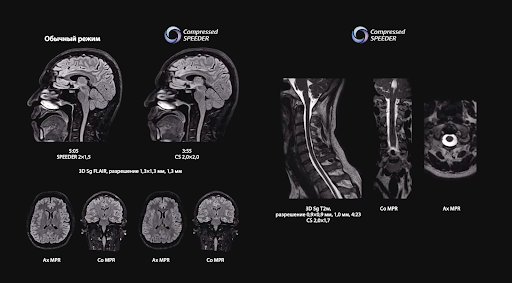

Vantage Orian обладает высокой производительностью благодаря интеллектуальной технологии быстрого сканирования. Эффективен при диагностике заболеваний в условиях ограниченного времени за счет применения таких технологий как Compessed SPEEDER и Fast 3D и увеличивает пропускную способность медучреждения.

Compessed SPEEDER